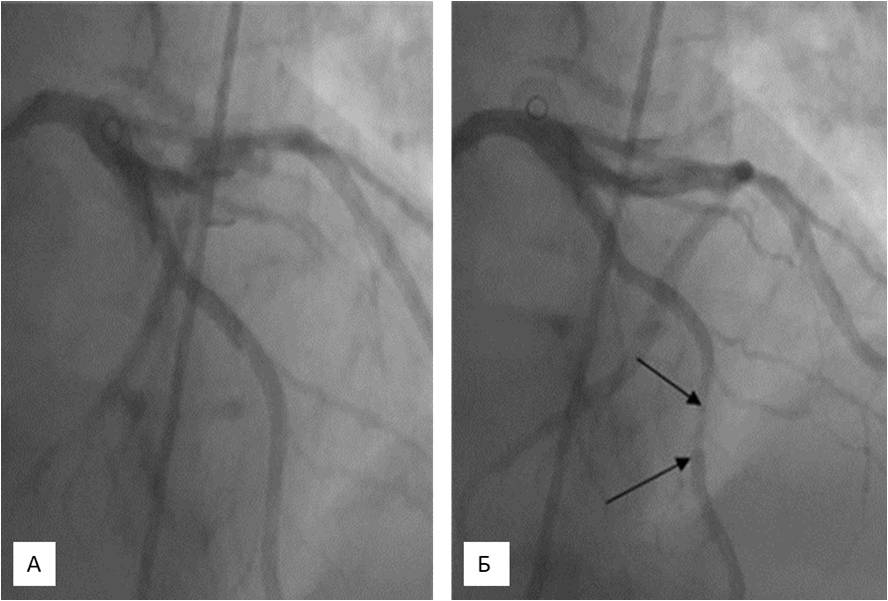

Coronary angiography (11/12/2014). Left type of circulation. The left CA trunk without changes. МB in the middle AIVA segment narrowing the lumen of the artery to 80% in systole (Figure 3). Stenosis of the orifice of the 1st diagonal branch to 60%, stenosis of the middle segment of circumflex artery to 50%. The right CA without changes.

Fig. 3. Coronary angiography (11/12/2014) of patient L. A myocardial bridge in the middle segment of the anterior interventricular artery (diastole (A), systole (B)) with compression of the artery in systole to 80% (arrows).